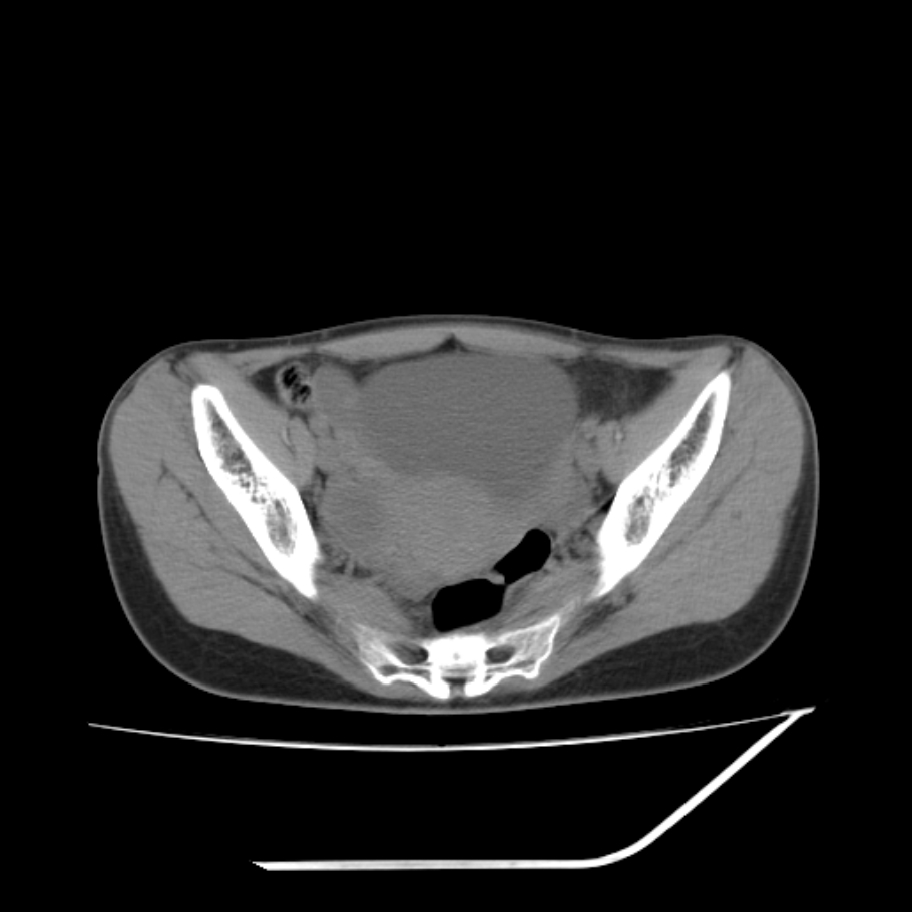

女,25岁。偶尔有右下腹不适感,余无明显异常。(结婚半年),囊壁较厚,是卵巢囊肿吗?

其上一层面见两枚小气泡影,考虑为肠管影可能,不完全除外囊肿

右侧卵巢区椭圆形囊性肿物,内壁光滑 无分隔。直肠子宫间隙内有少量积液征象。结合临床考虑卵巢巧克力囊肿,还要问问有没有痛经,本例ct怎么没有灌肠?要是灌肠或前一前口服造影剂,起码可以和肠管区别开

b超示:囊实性占位,畸胎瘤?临床有痛经。

考虑右侧卵巢囊性占位性病变(巧克力囊肿?),盆腔积液有不排除宫外孕可能,请结合临床和b超。

右侧卵巢囊伴盆腔少量积液。